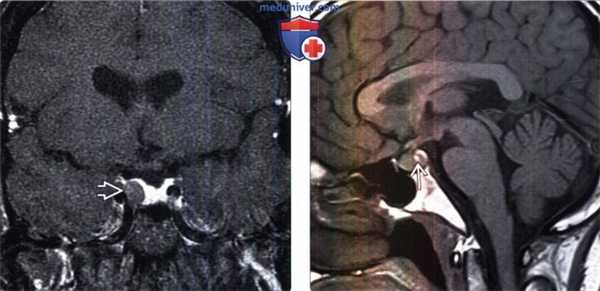

(Слева) МРТ, постконтрастное Т1 -ВИ, корональный срез: у пациента с акромегалией визуализируется микроаденома в виде объемного образования с менее интенсивным накоплением контраста, расположенного в правых отделах аденогипофиза. При резекции была выявлена соматотропинома.

(Справа) МРТ, Т1-ВИ, сагиттальный срез: у молодого взрослого мужчины с легким повышением уровня пролактина отмечается гиперинтенсивный очаг, не связанный с ярким нейрогипофизом и, вероятно, представляющий собой нефункционирующую микроаденому с геморрагическим компонентом. При кисте кармана Ратке может наблюдаться похожая картина.